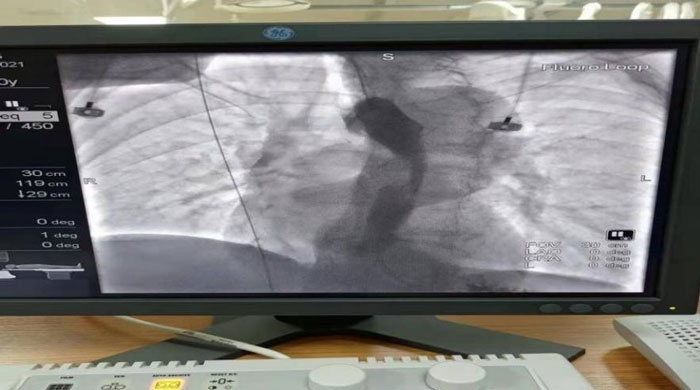

患者于2021年12月15日行“食管球囊擴(kuò)張+食管支架植入術(shù)”。術(shù)中在數(shù)字減影X光機(jī)透視下準(zhǔn)確定位示狹窄位于食管胸中段,長約6CM,管腔極度狹窄,僅少量造影劑呈線型通過,鉛標(biāo)標(biāo)記狹窄遠(yuǎn)近兩端;導(dǎo)絲引導(dǎo)下經(jīng)口、食道引入5f造影導(dǎo)管至胃內(nèi),造影確認(rèn)導(dǎo)管位于胃內(nèi),退出導(dǎo)管保留導(dǎo)絲,沿導(dǎo)絲引入球囊擴(kuò)張導(dǎo)管擴(kuò)張食管狹窄段。退出球囊保留導(dǎo)絲, 沿導(dǎo)絲將18mm*100mm型號(hào)食道支架放置于食管狹窄處,確認(rèn)位置合適后釋放推送器使支架擴(kuò)張,支架擴(kuò)張后退出推送器及導(dǎo)絲;再次口服造影劑可見食管全段通暢,支架擴(kuò)張良好,手術(shù)順利完成。

支架植入前造影,食管重度狹窄,僅少許造影劑線性通過